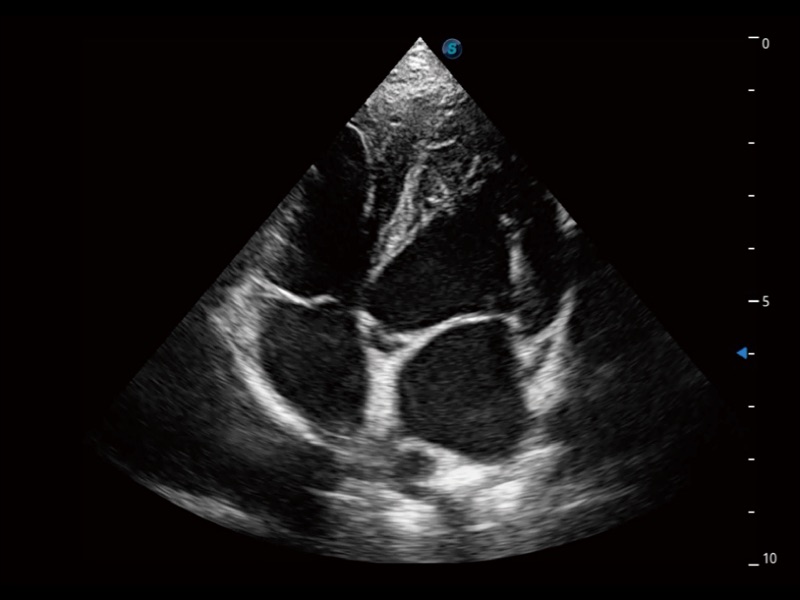

优异的基础图像

ProPet 70 全新的动物超声智能软件和丰富的探头群,为动物医生提供了高清晰度和精细分辨率的图像,无论在宠物、马科、畜牧还是实验室动物等应用中都可以轻松应对,为您的日常工作带来满意的体验。

(犬)四腔心

(犬)四腔心MQA

• AMM 解剖M型

通过360度任意调节3条M型取样线,在同一心动周期上观察心脏不同位置的运动曲线,得到准确的心功能测量数据,有效评估心肌运动及左心室功能。

• TDI 组织多普勒成像

实时用颜色表示心肌组织运动,观察和定量组织的运动情况,对快速检测与评估心肌的灌注和活性、电传导及心肌收缩和舒张功能等均能提供重要的诊断信息。